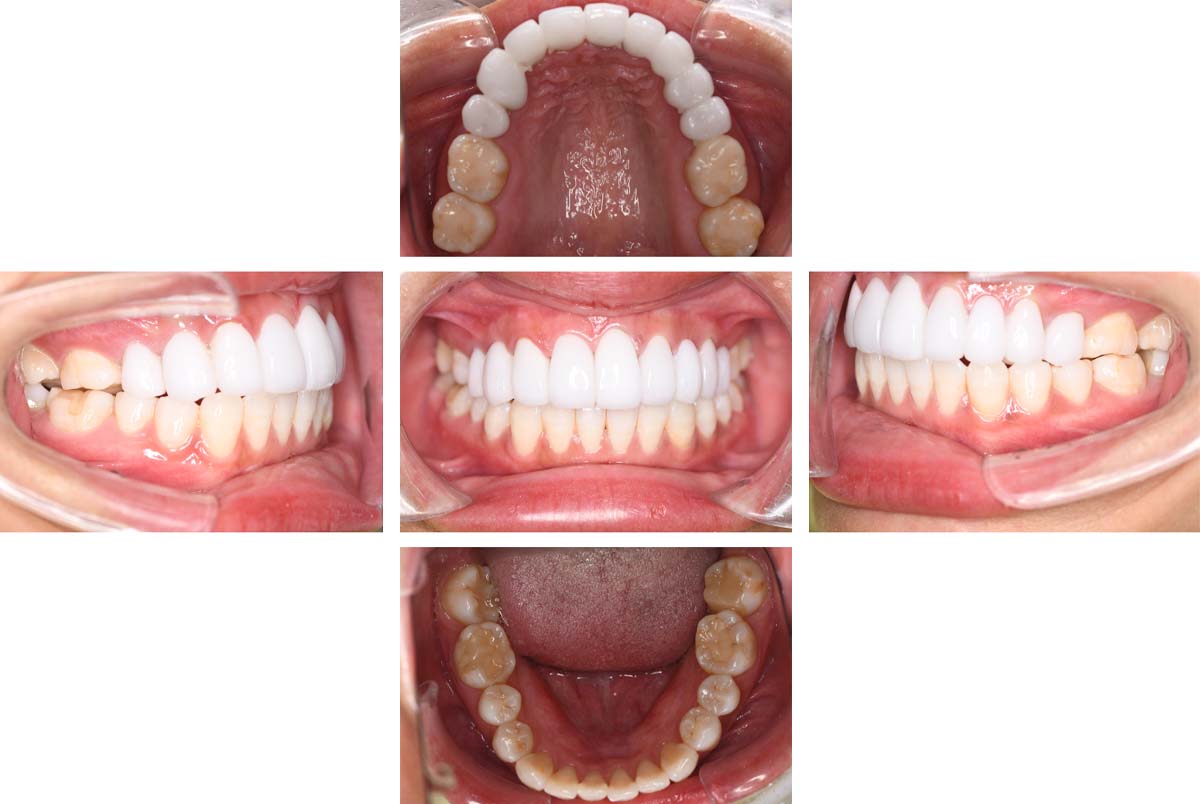

| 術後 |

|---|

![]() |

主訴:顎が疲れる

治療方針

マウスピースにて正しい噛み合わせの位置を確認し、習慣化したのち、咬合口腔内反映を行ないました。